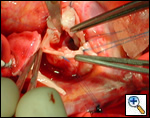

First coronary sinus incision in noncoronary sinus to facilitate exposure of the incisions into the coronary orifice sinuses.

In most cases, the right coronary artery sinus should be opened to the left of the coronary orifice and the left coronary artery sinus to the right of the coronary orifice. Occasionally one may not have enough room between a coronary orifice and the aortic valve; in this case the incision site should be tailored to the situation.

Ensure similar orifice sizes between the proximal and distal ascending aorta after patch augmentation by the use of a sizing dilator.